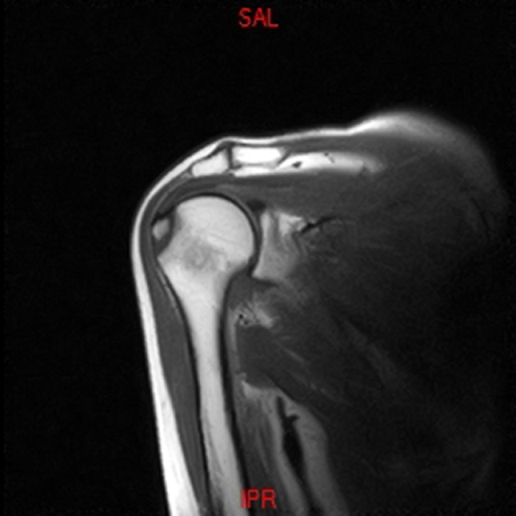

• RESONANCIA PATOLÓGICA DE HOMBRO - FRACTURA TROQUITER Y EDEMA OSEO -  COR T2 WF